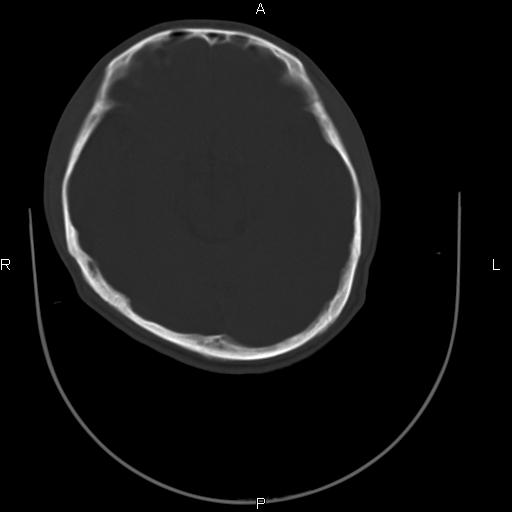

标题: CT27115:大家看一看,这孩子的颅骨表现? [打印本页]

标题: CT27115:大家看一看,这孩子的颅骨表现?

两名中学生打架,脑质内未见异常,未上传。

颅骨骨质未见异常。

颅骨未见骨折征象。

两例——颅骨结构正常,未见明显骨折征象。

感觉第2个颅缝密度高,额顶部板障有点厚,正常变异?地中海贫血?